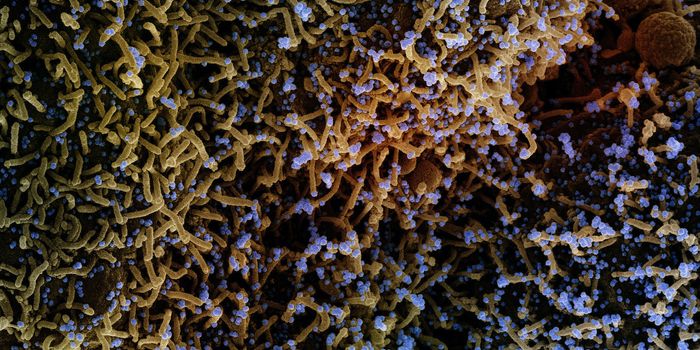

DEC 07, 2021Clinical & Molecular DXMore mutations, more transmissible, and more likely to infect vaccinated people—coronavirus variants such as Omicr ...